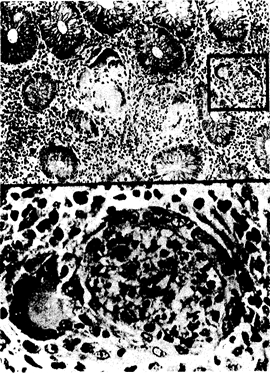

Рис. 150-2. Гистопатологические изменения при ПЛГ-проктите у активного мужчины-гомосексуалиста. Обратите внимание на наличие гранулематозных изменений с гигантскими клетками и крипта-абсцесс с прилегающей гигантской клеткой (вставка). Эти изменения сходны с теми поражениями, которые наблюдаются в прямой кишке при болезни Крона (из Т. С. Quinn et al„ N. Engl. J. Med., 305—195, 1981).

По мере того как расширялось использование бактериологических и серологических методов исследования при инфицировании С. trachomatis, стали выявлять все возрастающее число случаев заболевания ПЛГ-проктитом у гомосексуальных мужчин. У больных наблюдаются аноректальные боли и слизисто-гнойные кровянистые выделения из прямой кишки. Жалобы больных на понос обусловлены частыми болезненными, безуспешными попытками дефекации (тенезмы). При ректороманоскопии обнаруживают язвенный проктит или проктоколит, сопровождаемый выделением гнойного экссудата и кровоточивостью слизистых оболочек. Поскольку возбудитель ПЛГ является облигатным внутриклеточным патогеном, при гистологическом исследовании слизистой оболочки прямой кишки обнаруживают гранулемы с гигантскими клетками, а также крипта-абсцессы и обширное воспаление. Эти клинические и гистопатологические признаки, а также полученная при ректороманоскопии информация могут быть весьма сходными с соответствующими изменениями в прямой кишке, выявляемыми при болезни Крона (рис. 150-2).